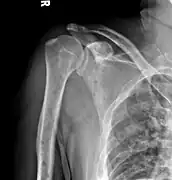

Medical imaging

The diagnostic examination of a person with suspected multiple myeloma typically includes a skeletal survey. This is a series of X-rays of the skull, axial skeleton, and proximal long bones. Myeloma activity sometimes appears as "lytic lesions" (with local disappearance of normal bone due to resorption). And on the skull X-ray as "punched-out lesions" (pepper-pot skull). Lesions may also be sclerotic, which is seen as radiodense.[47] Overall, the radiodensity of myeloma is between −30 and 120 Hounsfield units (HU).[48] Magnetic resonance imaging is more sensitive than simple X-rays in the detection of lytic lesions, and may supersede a skeletal survey, especially when vertebral disease is suspected. Occasionally, a CT scan is performed to measure the size of soft-tissue plasmacytomas. Bone scans are typically not of any additional value in the workup of people with myeloma (no new bone formation; lytic lesions not well visualized on bone scan).